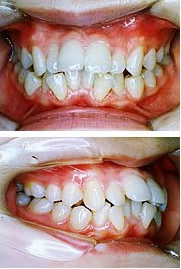

そうせい(八重歯・乱ぐい歯)、上顎前突(出っ歯)、反対咬合(うけ口)、開咬の4つに分けることができます。

顎が小さくて歯の生える場所が足らなくなり歯並びがデコボコになっています。

上顎の前歯が強く前に傾斜している場合と、下顎の成長が悪い場合があります。

前歯だけの反対咬合と顎の成長自体に問題がある場合(下顎前突)があります。

奥歯だけかんでいて前歯でかむことができない場合です。

舌の癖があり発音障害もあります。